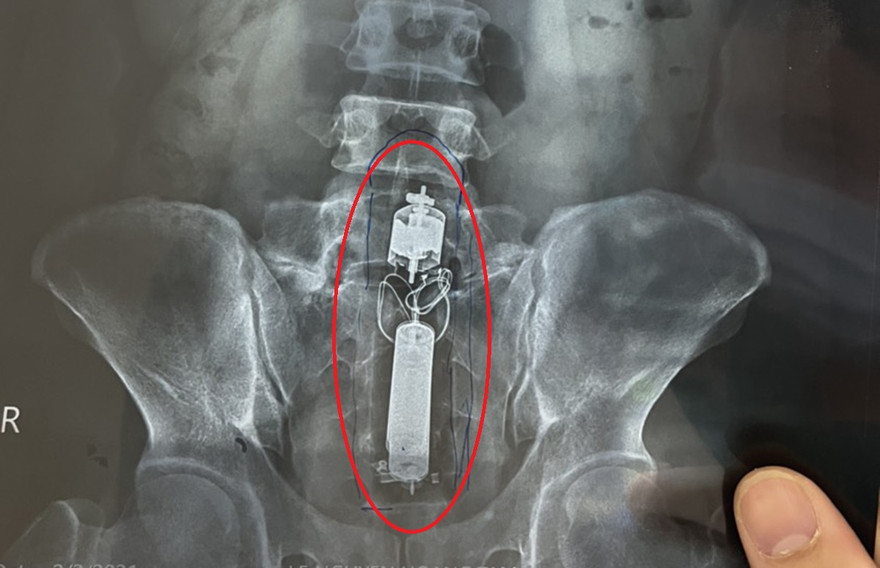

Sextoy kẹt trong trực tràng nam thanh niên.

Qua kiểm tra, các bác sĩ xác định sextoy lớn kẹt trong trực tràng bệnh nhân. Các bác sĩ quyết định không phẫu thuật mà cố gắng lấy dị vật bằng kỹ thuật nội soi. Tuy nhiên, do không có dụng cụ y tế chuyên dụng để lấy nên các bác sĩ mất gần 3 giờ vẫn không lấy ra được. Sau đó, bác sĩ tiến hành thụt tháo thì sextoy trôi xuống và được lấy ra thành công. Bệnh nhân đã xuất viện sau đó.